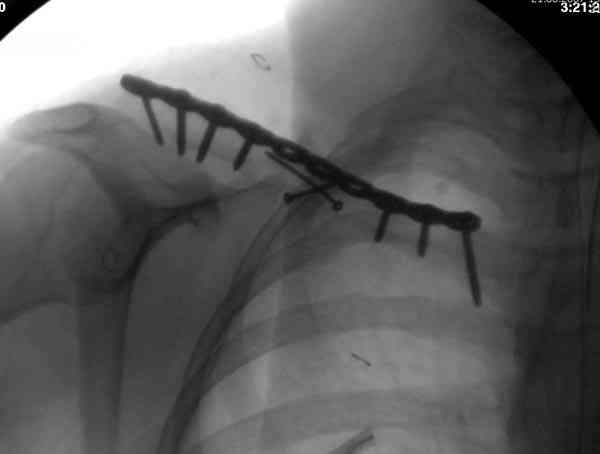

ГГШ> Результат стационарного лечения приведен на рентгенограмме (Xray_3).

Это картинка то есть через неделю после травмы, при выписке? Более чем приемлемо.

Евгений Чекашин: рутинно необходимо выполнение Рг графии в двух проекциях.

С этим трудно спорить, но имеем то, что имеем. Но если в существующей проекции, очевидно, нет контакта между отломками, так ли уж важно второе изображение? Даже если на нем мы увидим проекцию отломков друг на друга и по такой картинке кто-либо будет доказывать, что контакт есть?

Распределение мнений по перечисленным выше категориям приведено на гистограмме (см. Рисунок 1). Мнения разделись, и в аудитории преобладает убеждение, что сохранение смещения ключи.цы на величину диаметра без кортикального контакта между отломками и смещением до 3 см по длине у подростка 15 лет допустимо.

Оценка положения костных фрагментов должна осуществляться по рентгенограммам, вы.полненным в двух проекциях. Стандартная ( и почему.то считающейся достаточной в большинстве наших лечебных учреждений) передне.задняя проекция дополняется шейной проекций под уг.лом 45°. Смещения: расхождение в поперечном направлении, отсутствие кортикального контакта, укорочение ключицы более 1,5 см . недопустимы и должны быть устранены (11,12).